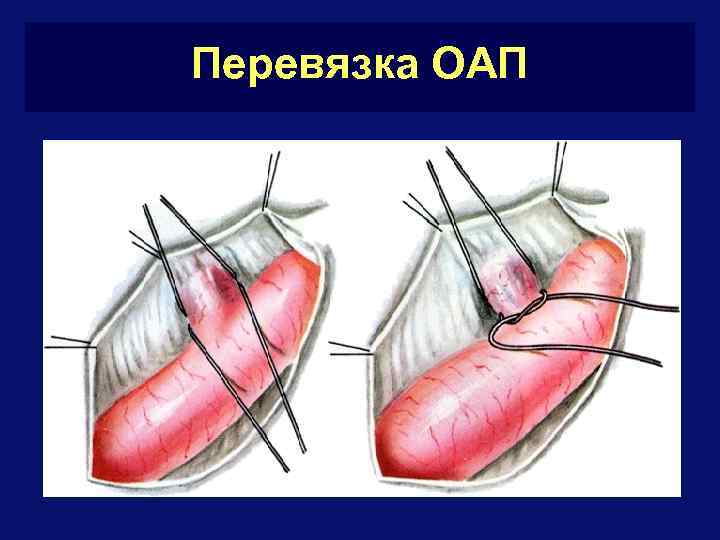

ОАП - лечение § Если ОАП функционирует более 6 мес. – абсолютное показание к операции, поскольку развитие легочной гипертензии у большинства больных неизбежно § Оптимальный возраст 2 -6 лет § Виды вмешательств: § открытая резекция и перевязка протока § торакоскопическое клипирование и пересечение протока § РЭ- окклюзия протока § Летальность – 0 -3%

Перевязка ОАП